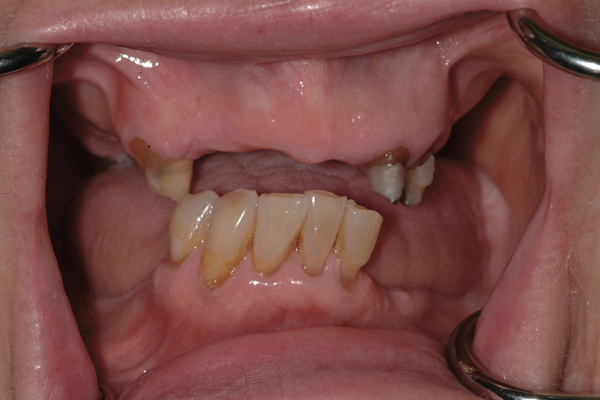

2. Potential “All-on-4” patient with terminal dentition who was unhappy with his smile esthetics.

Figure 2

Fig 17. Pre-treatment smile of patient with terminal dentition.

Figure 17

Fig 18. The patient’s intraoral condition.

Figure 18